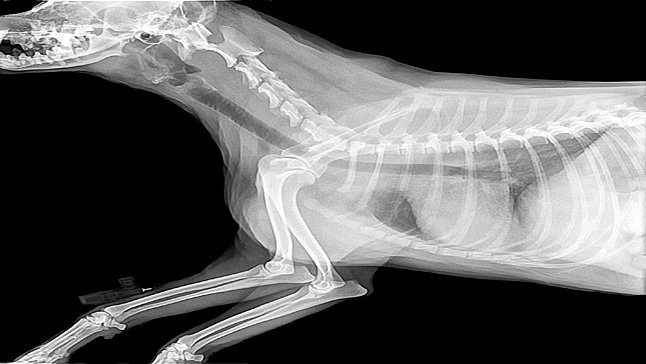

¿Sabías que el codo es una de las articulaciones más complejas que tienen nuestros perros?. Esta región tiene elevado interés veterinario debido a la cantidad de patologías que se diagnostican en ella, dando lugar a…